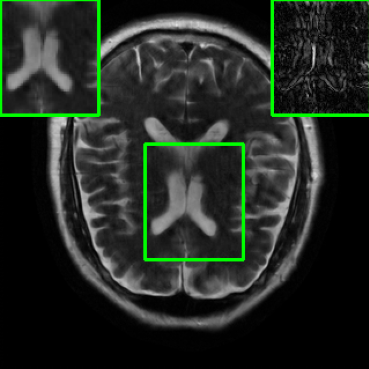

Results for the DIDN-based Reconstructor: To demonstrate adaptability to different network architectures, Table II compares reconstruction performance on the test set with the DIDN denoiser-based MoDL architecture. Average PSNR values with LONDN-MRI are compared to those with networks trained globally at different training set sizes. We ran only iteration of LONDN-MRI, where the reconstruction with a pre-trained (global) network was used to find neighbors. PSNR values for the oracle LONDN-MRI reconstructor are also shown. The overall performances with the DIDN-based architectures are better than with the UNet-based unrolled networks. The PSNRs for LONDN-MRI are consistently and similarly better than for the globally trained network across the different training set sizes considered, indicating potential for LONDN-MRI in improving state-of-the-art models. Fig. 6 visually compares reconstructions and reconstruction errors (in zoomed in region) for different methods. We can see that the LONDN reconstructors capture the original image features more sharply and accurately than the globally learned reconstruction.

| Ground Truth | Global | LONDN-MRI | Oracle |

| (1 iteration) | |||

![]() |

| PSNR = dB | PSNR = 34.15 dB | PSNR = 34.46 dB | PSNR = 34.54 dB |